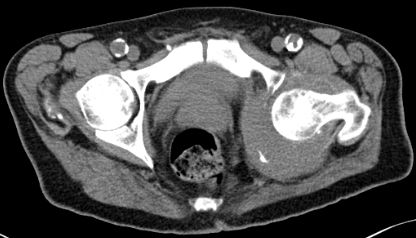

| Hüftpfanne | 74-jähriger Mann mit einem Adenokarzinom des rechten Lungenoberlappens pT1b pN2 Mo 1 Jahr nach Lobektomie Bestrahlung und

Chemotherapie. Die dorsalen Hüftpfannenteile links und Teile des Sitzbeins sind völlig zerstört.![]() |

Nach einem Sturz hat sich zusätzlich ein Haematom gebildet und der linke Hüftkopf hat sich nach dorsal verlagert.![]() |